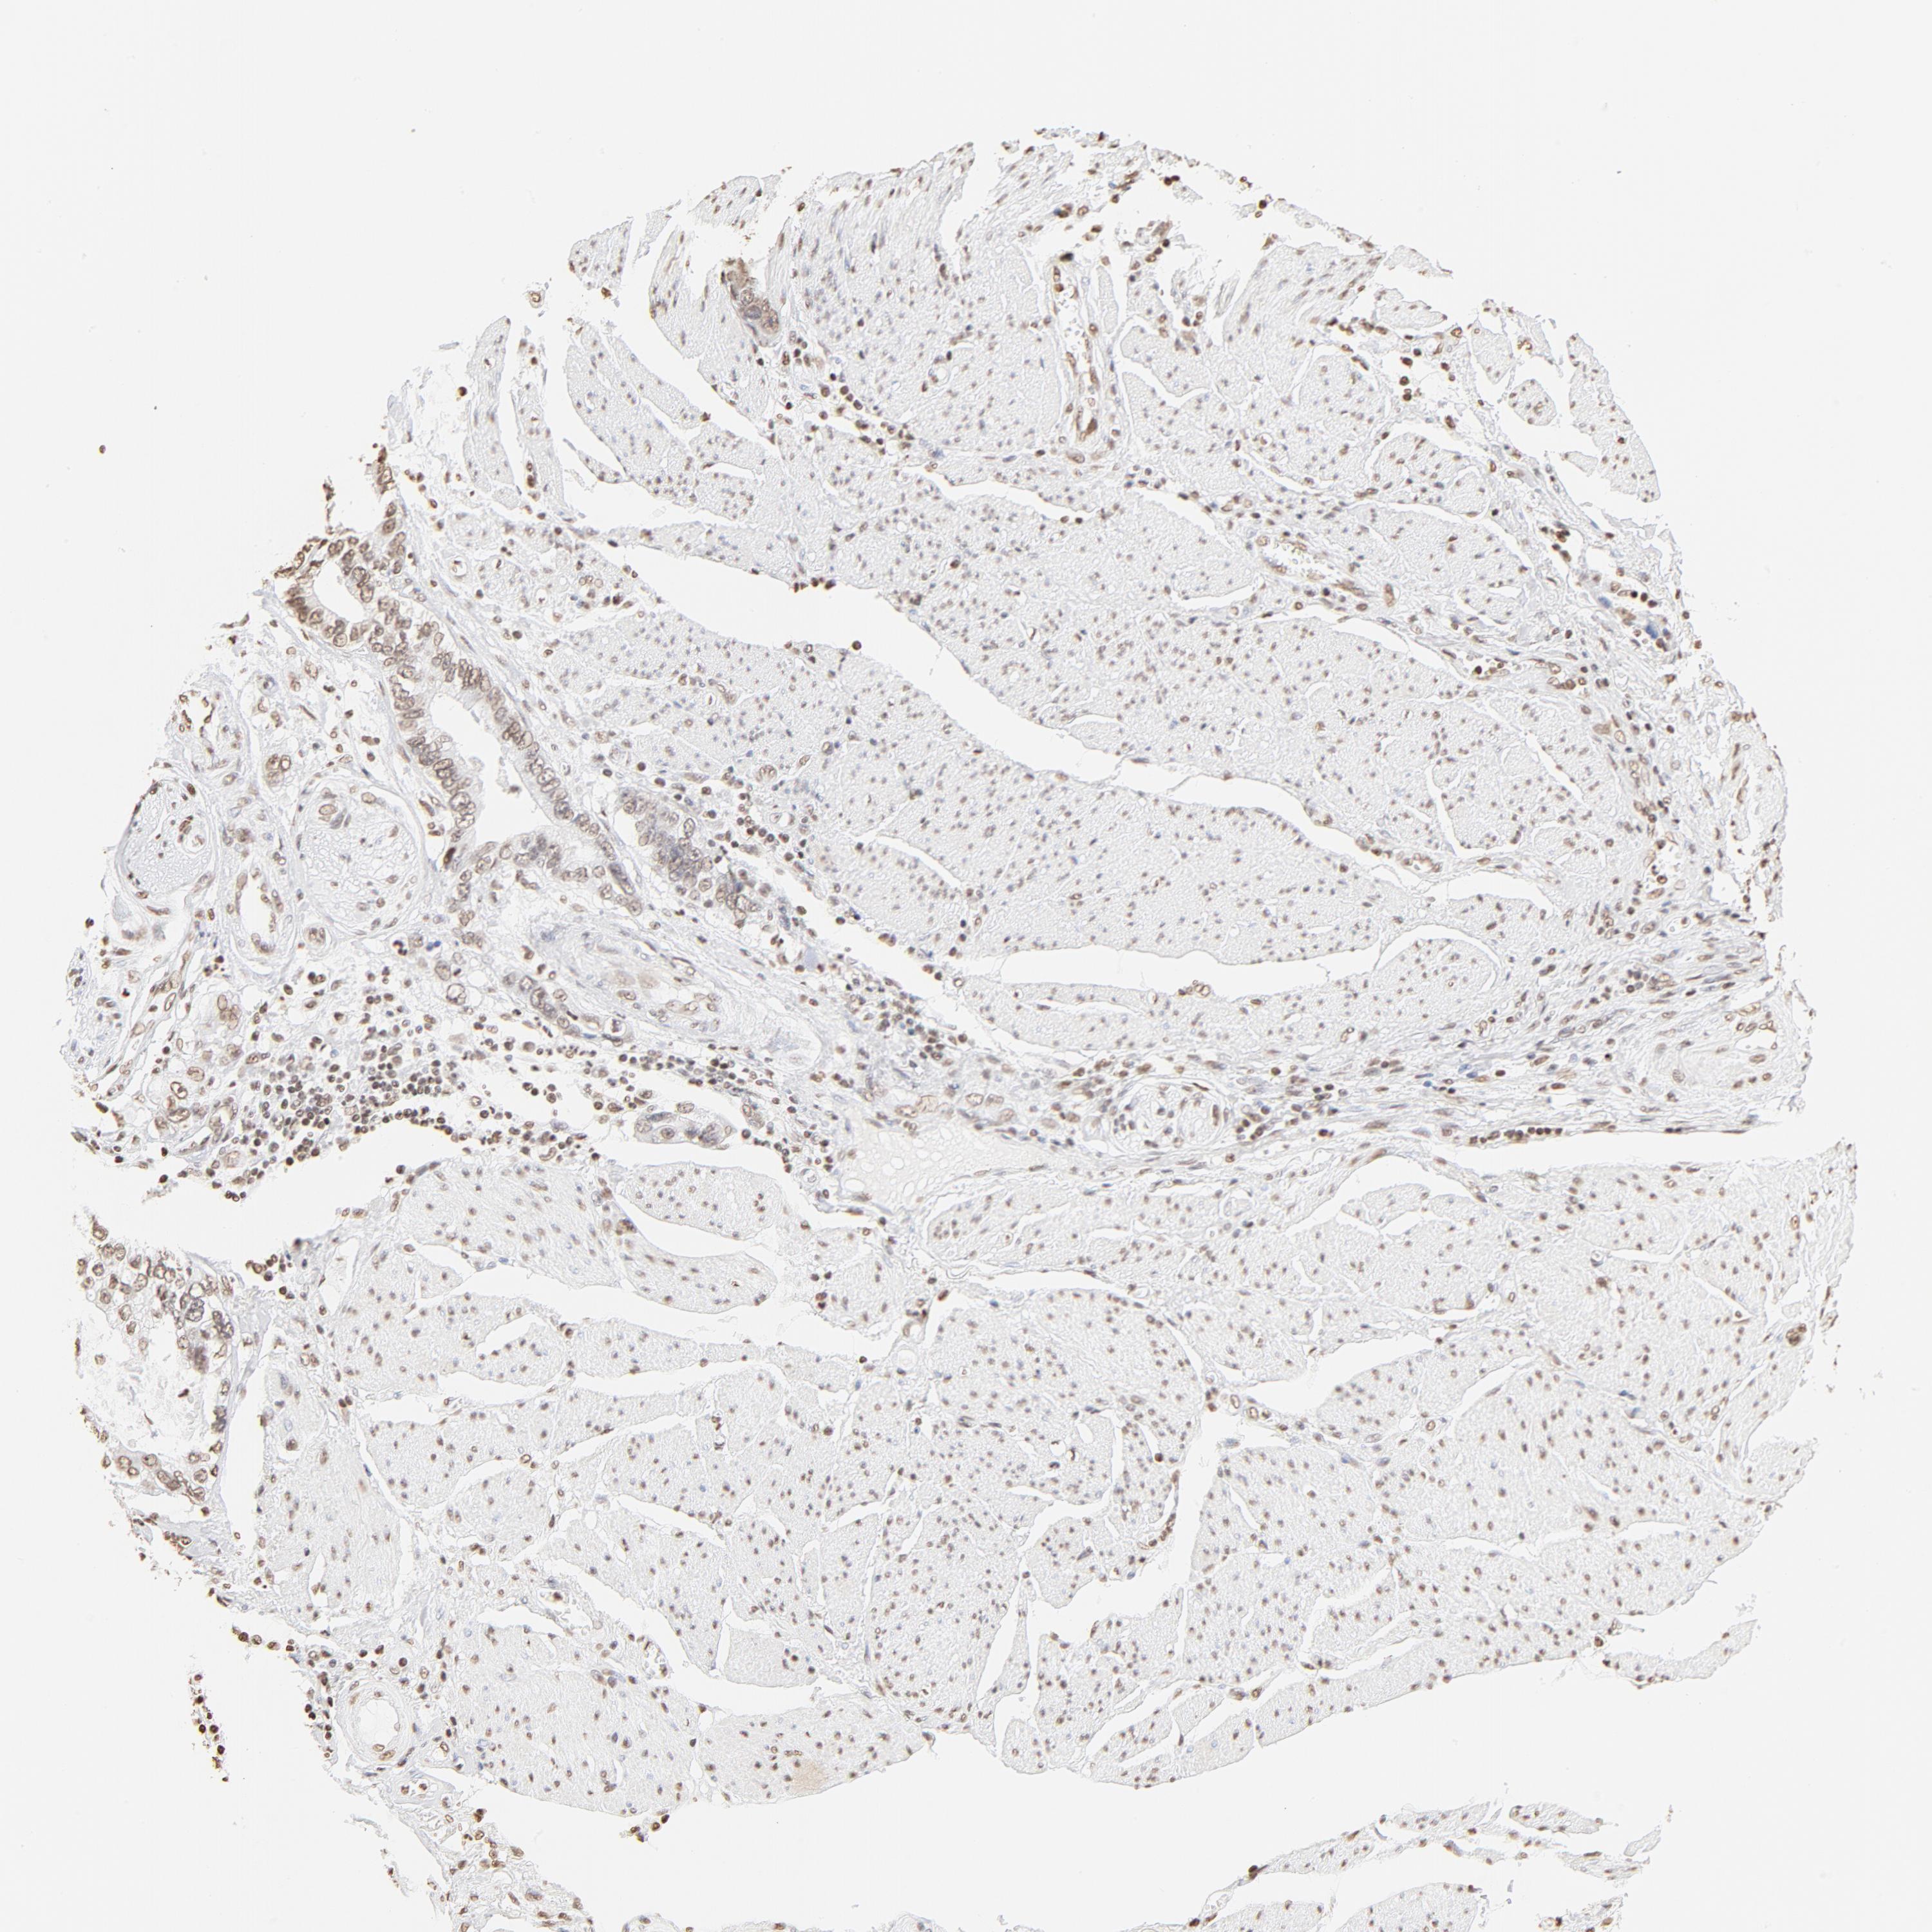

STOMACH CANCER - Protein expressioni

A mouse-over function shows sample information and annotation data. Click on an image to view it in a full screen mode. Samples can be filtered based on level of antibody staining by selecting one or several of the following categories: high, medium, low and not detected. The assay and annotation is described here.

Note that samples used for immunohistochemistry by the Human Protein Atlas do not correspond to samples in the TCGA dataset.

Antibody stainingi

Antibody staining in the annotated cell types in the current human tissue is reported as not detected, low, medium, or high, based on conventional immunohistochemistry profiling in selected tissues. This score is based on the combination of the staining intensity and fraction of stained cells.

Each image is clickable and will lead to virtual microscopy that enables deeper exploration of all samples and also displays staining intensity scores, fraction scores and subcellular localization as well as patient and tissue information for each sample.

Antibody HPA003444

Staining

High

Medium

Low

Not detected

Intensity

Strong

Moderate

Weak

Negative

Quantity

>75%

75%-25%

<25%

None

Location

Nuclear

Cytoplasmic/membranous

Cytoplasmic/membranous,nuclear

Adenocarcinoma, NOS